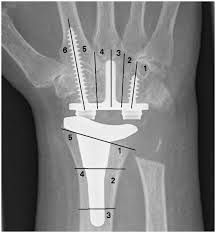

1) Radyal komponent hizalanması; Önkol (radius) anatomik ekseni ile hizalanır

2) Karpal komponent hizalanması; 3. metakarpal (uzun parmak) şaft ekseni ile hizalanır

Kritik nokta: Özellikle ulnar korteks referansı kullanılır. Çünkü Karpal blok doğal olarak hafif ulnar eğilimlidir. Bunun biyomekanik sonucu 3 noktada belirir.

“Radyal bileşeni önkol ekseniyle, karpal bileşeni uzun parmak metakarpal şaftının ulnar korteksiyle hizalamak…” diğer ifade ile; Radial component → radial shaft axis, Carpal component → 3rd metacarpal axis

Radial komponent → radius ekseni

“Karpal → 3. metakarpal”